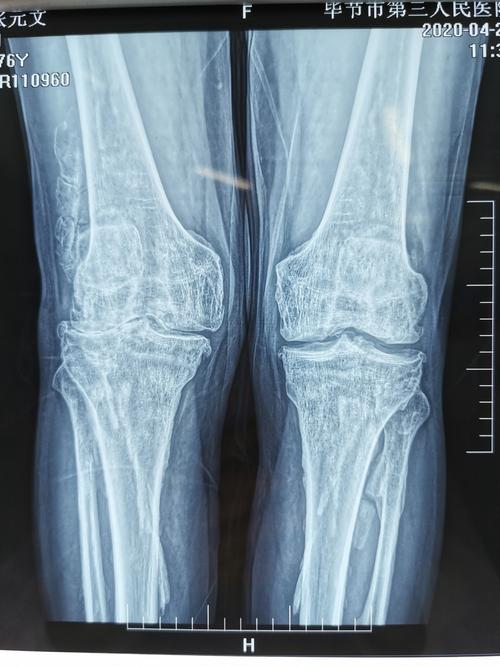

辟谣!膝关节长大量骨刺可以不手术,磨掉骨刺就能止痛并改善活动

ct提示双膝关节退变,双侧胫腓骨局部骨皮质增厚并条索状突起,骨刺增粗

膝盖长骨刺

膝关节骨质增生图片